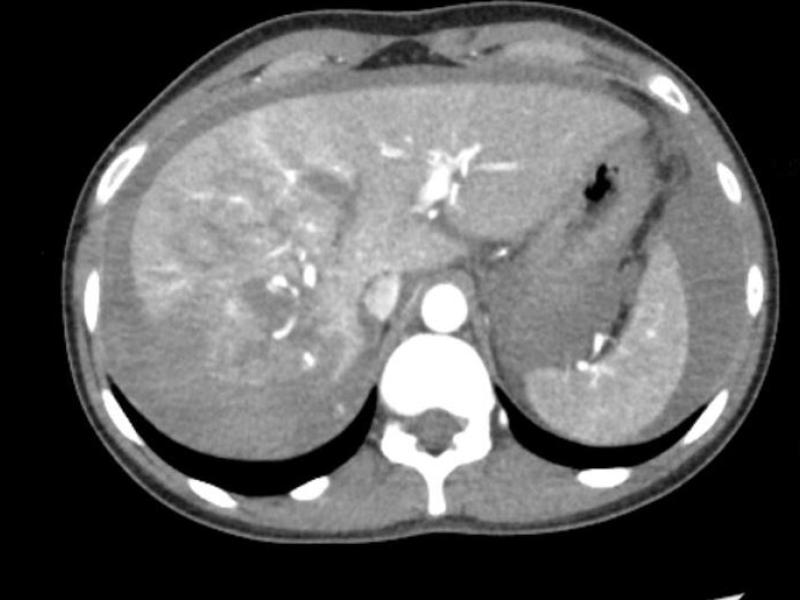

What's the diagnosis? By Dr. Abby Renko

A 50 yo female with a history of pancreatic cancer, on